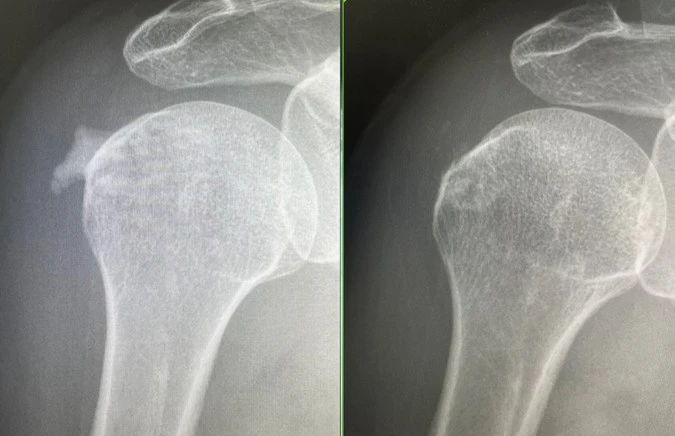

由於鈣化吸收期的鈣化質地較軟,可透過抽吸技術清除,陳臆文為個案安排「超音波導引注射與鈣化抽吸」治療,成功清除鈣化物並注射抗發炎藥物,以減輕疼痛與發炎。治療後,個案的疼痛明顯減輕,肩部活動功能逐步恢復,影像追蹤顯示,原本雲朵狀的鈣化物已消失近9成。

個案的肩旋轉肌腱出現雲朵狀鈣化(左圖),引發劇烈疼痛,所幸經治療後,鈣化病灶幾乎完全消失,肩膀功能也已恢復靈活自如(右圖)。(圖片來源:萬芳醫院提供)